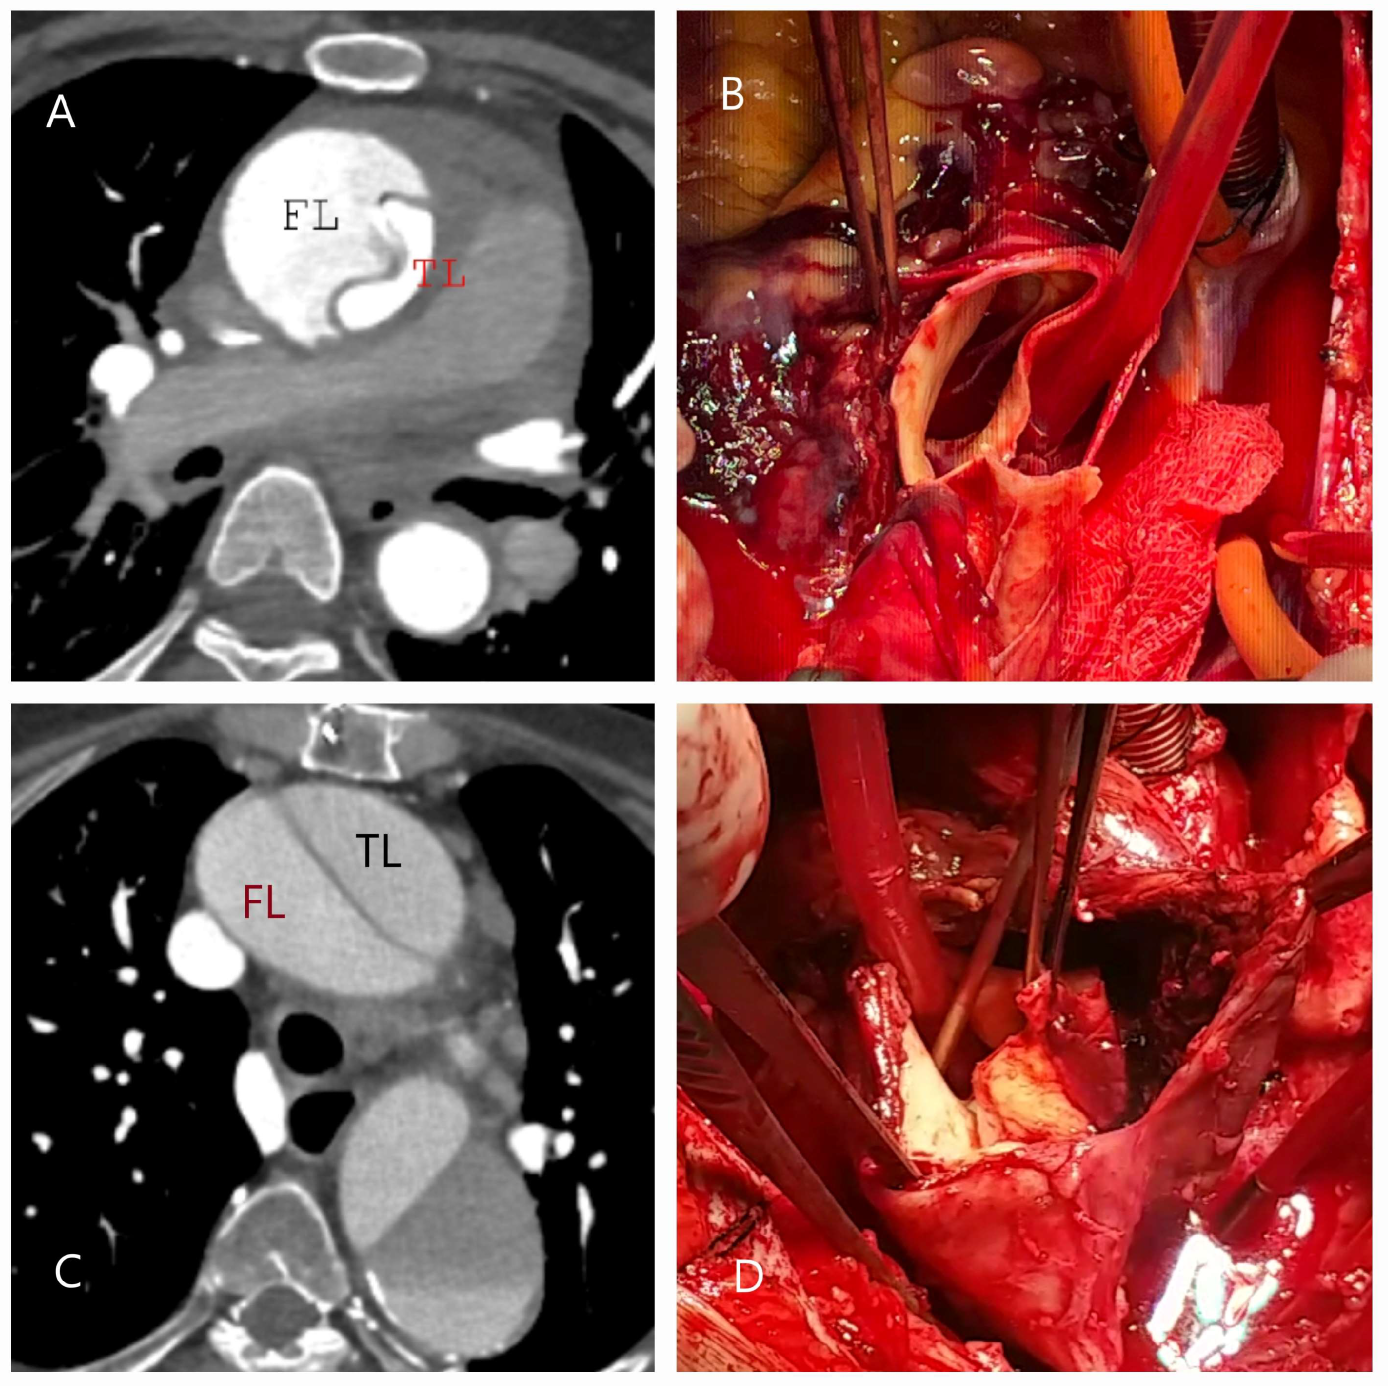

4.1. Dissection, Intramural Hematoma, and Penetrating Aortic Ulcer